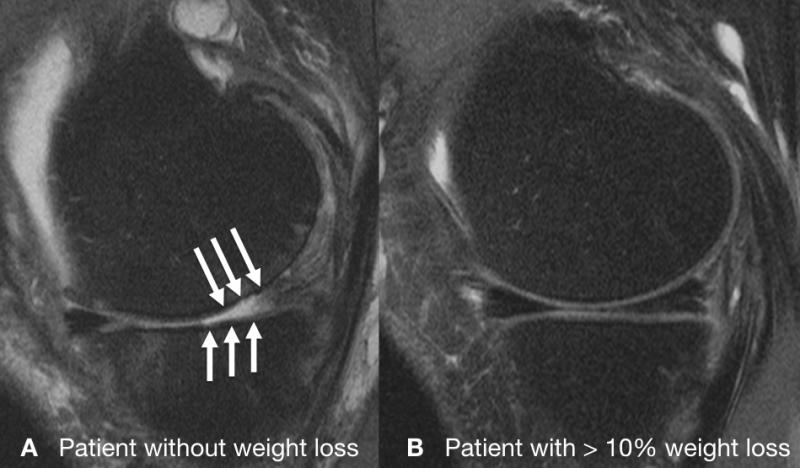

Gersing and colleagues recently investigated the association between different degrees of weight loss and the progression of knee cartilage degeneration in 506 overweight and obese patients from the Osteoarthritis Initiative, a nationwide research study focused on the prevention and treatment of knee osteoarthritis. The patients either had mild to moderate osteoarthritis or risk factors for the disease. They were divided into three groups: a control group who did not lose weight, a second group who lost a little weight, and a third group who lost more than 10 percent of their body weight. The researchers then used MRI to quantify knee osteoarthritis.

"Through T2 relaxation time measurements from MRI, we can see changes in cartilage quality at a very early stage, even before it breaks down," Gersing said.

When the researchers analyzed differences in the quality of cartilage among the three groups over a four-year time span, they found evidence that weight loss has a protective effect against cartilage degeneration and that a larger amount of weight loss is more beneficial.

"Cartilage degenerated a lot slower in the group that lost more than 10 percent of their body weight, especially in the weight-bearing regions of the knee," Gersing said. "However, those with 5 to 10 percent weight loss had almost no difference in cartilage degeneration compared to those who didn't lose weight."